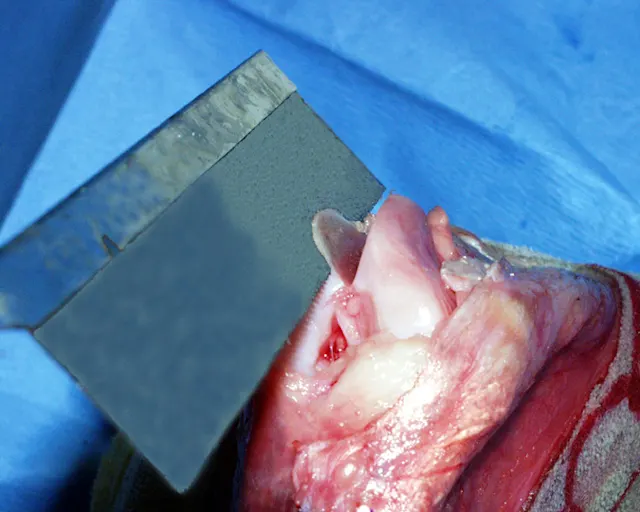

I typically perform a lateral arthrotomy because imbrication of the soft tissues on the lateral side is necessary. Once the arthrotomy is performed, the trochlear groove is assessed. The trochlear groove depth should be approximately half the thickness of the patella (A): The red area is parapatellar fibrocartilage; the yellow oval designates the patella and demonstrates the depth of the trochlear groove (normally 50% of the patellar thickness). The trochlear groove in B (an example from a clinical case) is absent and trochleoplasty is clearly required.

A

One way to deepen the trochlear groove is the wedge recession technique. This technique requires use of a small hobby saw to create cuts in the distal femur, freeing up a wedge of bone with cartilage attached. The wedge is removed, the bed from which the wedge was taken is deepened, and the bone/cartilage wedge is replaced. Although the pictures presented here are from a normal stifle, the method of performing the procedure applies to the clinical case.